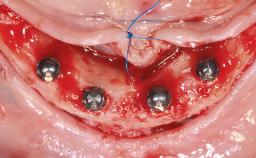

Treatment of the Atrophic Maxilla Using Two Standard Implants and Two Zygomatic Implants Immediately Loaded with a Fixed Restoration

A 65-year-old woman was referred to our clinic by another dentist she had recently visited and who had diagnosed a compromised and complex clinical and anatomical situation. She complained of pain and difficulty when chewing, instability of her maxillary prosthesis, and unsatisfactory esthetics. She had received maxillary implants restored with partial fixed dental prostheses, but no stable clinical solution had been achieved. She expressed a preference for a fixed maxillary rehabilitation.